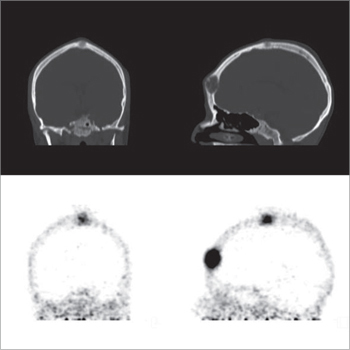

Cáncer medular de tiroides

El tumor medular de tiroides es una neoplasia poco frecuente (3-5% de todos los cánceres de tiroides) proveniente de las células C parafoliculares (Figuras 6 y 7). La mayoría ocurre en forma esporádica (70-80% de los casos) pero existen formas familiares (solos o como parte del síndrome NEM 2A y 2B)20. Este tumor metastiza precozmente a los ganglios cervicales (55-75% de los casos), principalmente el compartimiento central del cuello. Metástasis a distancia se encuentran en 10-15% de los pacientes, principalmente mediastino, pulmones, hígado y hueso21 (Figuras 8 y 9). Debido a la producción de calcitonina por las células C, esta hormona es usada como marcador tumoral al diagnóstico y durante el seguimiento. La resección quir úrgica completa (tiroidectomía total y disección cervical amplia) es la únicaforma de curación. A pesar de la agresividad de este tratamiento, 40% de los pacientes operados mantienen niveles de calcitonina medibles y otro 10% inicialmente negativo, recurrirá en el tiempo2. Por esta razón, la localización de cualquier cúmulo tumoral existente mediante imágenes es de extrema importancia. Los criterios usados en imágenes diagnósticas para el tumor primario son similares a los usados en el cáncer diferenciado de tiroides, sin embargo, la localización de adenopatías y metástasis a distancia es generalmente difícil22. Convencionalmente se ha usado ecografía, tomografía computada y cintigrafía (In111-pentatreotide, Tc99m-DMSA- V y Tc99m-MIBI) para evaluar pacientes con enfermedad recurrente. Tc99m(V)-DMSA (ácido dimercaptosuccínico pentavalente) es un marcador tumoral inespecífico. El mecanismo de captación es sólo parcialmente conocido y tendría relación con la presencia de grupos fosfatos y el pH del medio. Su uso en esta enfermedad fue descrito por primera vez en 1984 por Ohta23. La sensibilidad reportada de la cintigrafía con DMSA-V se encuentra entre 50-80% y su uso combinado con In111- pentatreotide alcanza 86%24. F18-FDOPA es un aminoácido (dihidroxifenilalanina) marcado con Flúor18 usado originalmente para el estudio de pacientes con enfermedad de Parkinson. Los tumores neuroendocrinos pueden captar y decarboxilar p recursores de aminoácidos tales como la DOPA y ser visualizados con PETFDOPA. Las series reportan sensibilidades entre 44 y 90% para este método2. Desafortunadamente para la síntesis de F18-FDOPA se requiere de blancos especiales en el ciclotrón (diferentes a los usados para la producción de FDG) y de módulos de síntesis dedicados, lo que hace que este radiofármaco aún no esté disponible en nuestro medio. Si bien el 85% de los tumores medulares de tiroides expresan algún tipo de receptores de somatostatina y 75% expresan los tipos 2,3 ó 5 (que son los afines por octreotide), el subtipo 2 es expresado sólo en 43%25, que es el blanco principal de los análogos disponible para imagen y terapia. La afinidad de estas moléculas por los subtipos 3 y 5 es típicamente menor. Esto explica la variabilidad de resultados en la literatura en relación con la sensibilidad tanto de la cintigrafía con In111-pentatreotide (Octreoscan) como para el PET con derivados de la somatostatina para la detección de esta neoplasia. Las series publicadas con In111-pentatreotide reportan sensibilidades entre 50-75% para cáncer medular de tiroides y sugieren que este método es mejorpara metástasis ganglionares en el cuello o mediastino que para metástasis a distancia2. Estudios con PET y análogos de somatostatina son escasos para esta enfermedad. La limitada información disponible sugiere que la sensibilidad de PET-análogos de somatotatina es inferior al PET-FDOPA en cáncer medular de tiroides tanto a nivel de paciente como de lesión y similar a los resultados de estudios realizados con PET-FDG. En el trabajo retrospectivo de Conry et al2, se estudiaron 18 pacientes con recidiva de cáncer medular de tiroides a los que se le realizó PET con Ga68-DOTATATE y F18-FDG. La sensibilidad encontrada por paciente fue 72% para DOTATATE y 78% para FDG. FDG encontró 28 metástasis mientras que DOTATATE 23. Treglia et al26 recientemente publicó una serie prospectiva de 18 pacientes con recurrencia de cáncer medular de tiroides estudiados PET y Ga68-análogos de somatostatina, F18-FDOPA y F18-FDG. En este trabajo la sensibilidad por paciente fue 72% para FDOPA, 33% para análogos de somatostatina y 17% para FDG. A nivel de lesiones la sensibilidad fue: 85% para FDOPA, 20% para análogos de somatostatina y 28% para FDG.